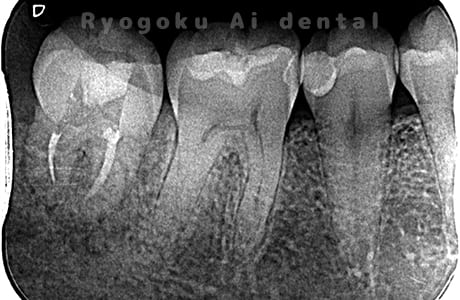

Case02

-

- 原因

- C4

- 治療期間

- 3ヶ月

- 治療内容

- 自家歯牙移植手術+マイクロエンド+ダイレクトボンディング

- 治療費用

- 220,000円

他院で虫歯が大きく、抜歯と判断され、インプラント手術を提案された患者様です。親知らずが残存していたため、自家歯牙移植手術を行いました。

<リスク・副作用>

治療後、痛みや違和感、出血、腫れなどが出る事があります。喫煙者、糖尿病などの方の場合、歯が生着しない場合があります。